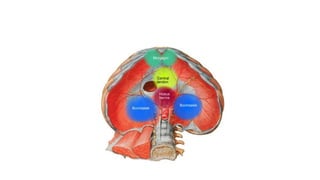

HIATUS HERNIA

TYPES OF HIATUS HERNIAS